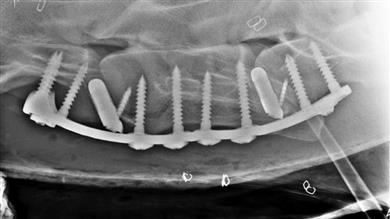

During surgery, the injured horse is anesthetized and placed in a surgical hammock to immobilize it. The fracture is stabilized with a 3D-printed plate and 3D-printed cancellous screws bridging the vertebrae, and depending on the case (and the vertebrae affected) with a small 3D-printed titanium cage applied in the ventral disc space. Cancellous or cortical screws may sometimes be associated with the locked screws to allow compression of the fractured fragment.

The benefit of this assembly lies in the fact that the 3D-printed titanium intervertebral spacer used during surgery makes use of compression forces to preserve the spacing between the vertebrae, thus preventing the protrusion of the disc in the medullary canal and the ventral displacement of the caudal vertebra.

The shape of the plate allows the placement of three screws in each vertebra. In addition, implants manufactured using titanium alloys have shown better osseointegration than steel implants. And unlike conventional machining, metal 3D printing allows for the creation of porous patterns that facilitate the growth of bone through the cage and the fixation of the bone onto the cage.

Finally, the screws used are self-tapping and partially self-drilling, which allows maximum anchorage (close to the medullary canal) while reducing the risk of perforation during drilling or tapping. In Rossignol's experience, the use of a Redon drain limits this risk. Screw disinsertion or pullout may occur, but it is likely to be due to technical errors or associated with poor contact between the plate and the bone surface.

"The three major features and benefits of the metal 3D implant are its precision of custom printing and its resistance to a force and weight (a horse’s weight is significantly greater than a human’s), as well as the post-operative mobility of the animal," said Rossignol.